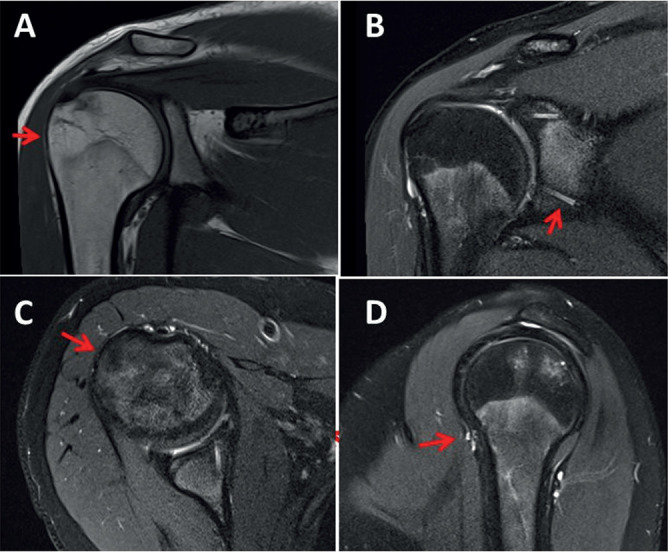

Case report: The patient is a 19-year-old female with hypermobile EDS manifested by frequent dislocations of large joints and small fiber neuropathy (SFN) presenting as recurrent syncope. The dislocations occurred spontaneously or triggered by voluntary or involuntary movements with such frequency, even during the night, that sleep was disturbed. The maximum sleep duration was between 4 and 5 hours. Bedding, analgesics, muscle relaxants and physiotherapy only marginally improved the pain and discomfort caused by the dislocations.